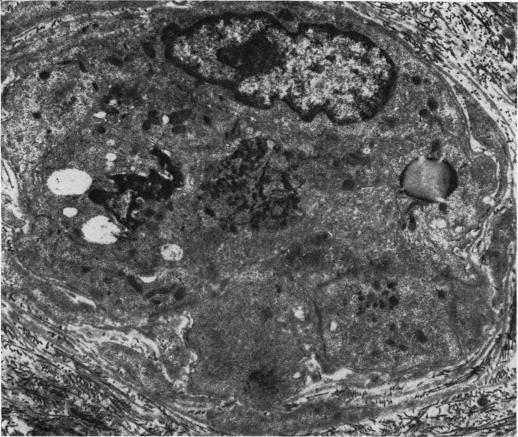

the results of an electron microscopical study of sural nerve biopsies from 11 patients with diabetic neuropathy are presented. Thrombi were seen in six cases in at least one intraneural vessel; nine cases showed hyperplasia of endothelial cells, and in seven out of these nine the hyperplasia was sufficient to occlude completely the lumen of small vessels; six cases showed degenerate pericytes and endothelial cells, and in some cases endothelial cells had been shed from the vessel wall, exposing the blood within the vessel to the underlying basement membrane; in five cases large lipid droplets were seen within endothelial cells. Abnormalities of the vessel wall would result in decreased fibrinolytic activity and a reduction of the antiplatelet aggregating proprties of the vessel. Desquamation of endothelial cells from the vessel wall, with exposure of platelets to underlying collagen, may act as a trigger for thrombus formation, particularly as the blood of diabetic patients is often in a hypercoagulable state. The significance of hyperplasia of endothelial cells is at present unknown but, once established, this too would result in profound alterations of loal blood flow and ischaemia of nerve. Damage to endothelial cells may also allow seepage of haematological constituents into the vessel wall, resulting in its progressive thickening.

本文展示了对11例糖尿病性神经病变患者腓肠神经活检的电子显微镜研究结果。在至少一条神经内血管中,6例可见血栓;9例显示内皮细胞增生,其中7例增生足以完全阻塞小血管腔;6例显示周细胞和内皮细胞变性,在某些情况下,内皮细胞从血管壁脱落,使血管内的血液暴露于下方的基底膜;5例在内皮细胞内可见大脂滴。血管壁异常会导致纤溶活性降低以及血管抗血小板聚集特性降低。内皮细胞从血管壁脱落,使血小板暴露于下方的胶原蛋白,可能触发血栓形成,特别是因为糖尿病患者的血液通常处于高凝状态。目前尚不清楚内皮细胞增生的意义,但一旦形成,这也会导致局部血流的深刻改变和神经缺血。内皮细胞损伤还可能使血液成分渗入血管壁,导致血管壁逐渐增厚。